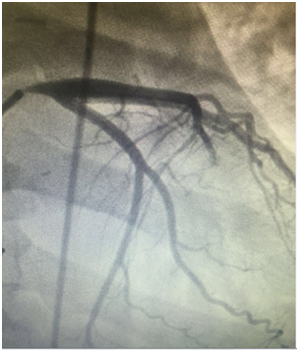

She was admitted to the emergency department. She reported a chronic fatigue and claudications of the upper limbs. The physical examination showed a significant asymmetry in pulses and blood pressure between right and left limb. All right pulses were absent with souffle on right subclaviar artery her blood pressure was 80/40mmhg in the right arm and very high in the left arm. The 12 lead electrocardiogram showed sinus tachycardia at 130bpm and diffuse repolarization abnormalities, ST-segment depression of 2-5mm in anterior, septal, apical and lateral derivations, and T-wave inversion in lateral derivations. As the diagnosis of non ST elevation myocardial infarction was made, the patient was referred to the cardiological department. Coronary angiography (Figure 1) revealed a severe stenosis (70-90%), 16-20mm of length of the left main coronary artery. There were no lesions in the other coronary arteries. The 2-dimensional transthoracic echocardiography showed an impaired left systolic function, regional wall-motion abnormalities , with a left ejection fraction of 0.35,high filling pressure, secondary pulmonary hypertension in addition to a moderate mitral regurgitation ,a moderate aortic regurgitation, and a good right systolic function.

Figure 1 Coronary angiography: Left main coronary severe stenosis.